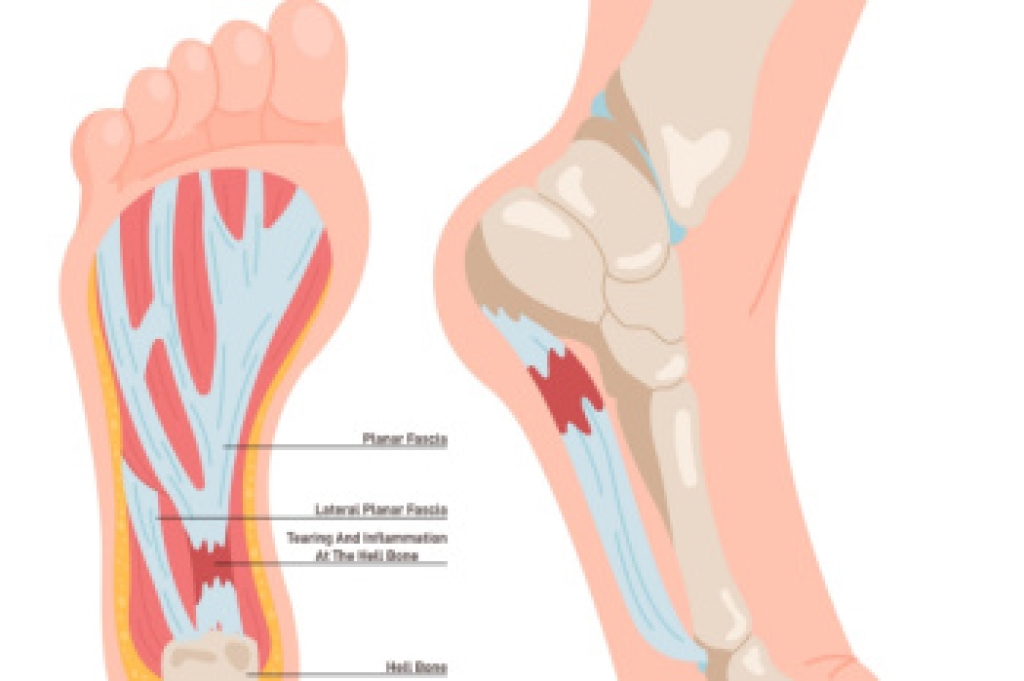

High arch pain, or pes cavus, occurs when the foot has an unusually high arch. This puts extra stress on the ball and heel of the foot. Common symptoms include pain, instability, and difficulty walking. Other issues include metatarsalgia, calluses, ankle arthritis, and Achilles tendonitis. High arch pain can be caused by neurological disorders, muscle imbalances, or previous injuries. A podiatrist can help by assessing the foot’s structure and offering treatments, such as custom orthotics and specialized footwear. In more severe cases, surgery may be needed to relieve pain and improve foot function. If you are experiencing pain in the arch of the foot, it is suggested that you schedule an appointment with a podiatrist for a diagnosis and appropriate treatment options.

Podiatric biomechanics is a particular sector of specialty podiatry with licensed practitioners who are trained to diagnose and treat conditions affecting the foot, ankle and lower leg. Biomechanics deals with the forces that act against the body, causing an interference with the biological structures. It focuses on the movement of the ankle, the foot and the forces that interact with them.